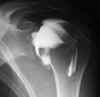

Letsels aan pezen en/of ligamenten van het gewricht |

Letsels van het gewrichtskapsel |

Ontwrichting |

Bot of kraarbeenletsels |

Gewrichtsmuizen (dit zijn kleine stukjes bot die los in

het gewricht voorkomen) |

Eventueel ontkleden van de punctieplaats, zoals

schouder, heup, ... |

Ruim ontsmetten van depunctieplaats om alle

besmettingsrisicos uit te sluiten |

Voor het inspuiten van het contrast wordt er best een

foto genomen van het te onderzoeken gewricht. |

De patiënt van de onderzoekstafel helpen (oppassen

voor syncope) |

De patiënt zonodig helpen aankleden, het onderzocht

gewricht moet zo weinig mogelijk worden belast, denk eraan dat het

onderzoek nu nog niet is afgelopen |

De patiënt zo snel mogelijk naar de CT-scan brengen